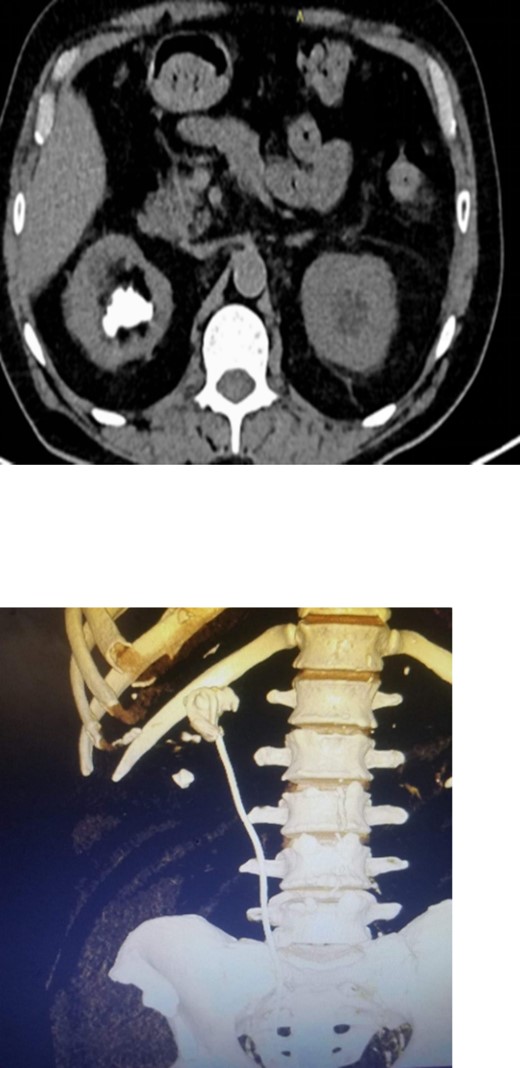

On physical examination, he had normal vital signs, no fever, and exhibited mild tenderness in the suprapubic area and right costovertebral angle. The results of the laboratory tests were normal, and the serum creatinine level was 0.8 mg/dl. Urine culture was negative for bacteria. Preoperative abdominal and pelvic ultrasound revealed two right renal stones, one measuring 4 cm in the upper pole and 2 cm in the lower pole with mild hydronephrosis, along with a large bladder stone measuring 6 cm, and a shadow of a double J stent. A computed tomography (CT) scan confirmed the presence of a 4 cm upper pole renal stone, a 1.8 cm lower pole renal stone, significant proximal pigtail calcification with mild hydronephrosis (Fig. 1A and B), and a 6 cm bladder stone deeply embedded in the distal pigtail (Fig. 2A and B). Additionally, small intrarenal stones were observed on the left side, along with a proximal ureteric stone measuring 8 mm by 9 mm with mild hydronephrosis.

Non-contrast CT scan showed giant bladder stone profoundly embedded in the distal pigtail of the DJ stent.